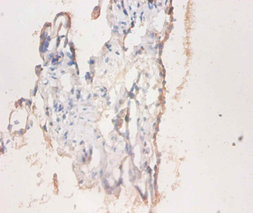

DescriptionCD59 Polyclonal Antibody. Unconjugated. Raised in: Rabbit.

ApplicationELISA, IHC, IF; Recommended dilution: IHC:1:20-1:200